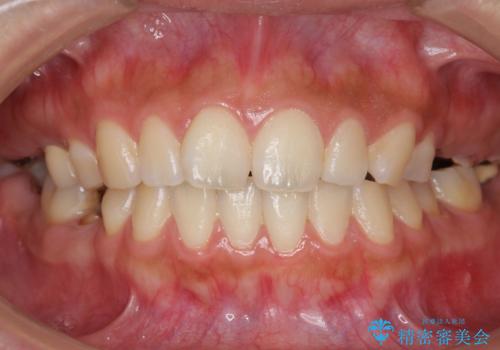

インプラントや入れ歯を使わずに奥歯でしっかり咬むことができるようになり、また見た目も自然だと大変喜んで頂けました。

クラウンの種類:メタルボンドクラウン エコノミー フルベイク